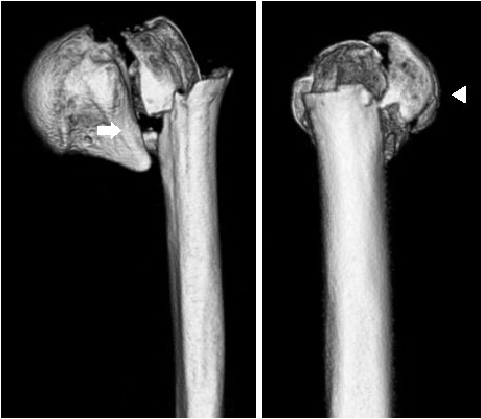

Shoulder joint dislocation has the most common incidence rate compare compared to other joints. It is reported that shoulder Shoulder dislocation couldmay be associated with glenoid rim, greater tuberosity of humerus and coracoid process fracture. There were have only been 2 cases of anterior shoulder dislocation simultaneously combined with simultaneous glenoid rim, coracoid process, and humerus greater tuberosity fracture worldwide and no report reports in Korea. We present a case of quadruple fracture (glenoid rim, coracoid process, greater tuberosity, surgical neck of humerus) associated with anterior shoulder dislocation and treated successfully by open reduction. In addition, with we provide the injury mechanism, diagnosis, treatment procedure and discussion.